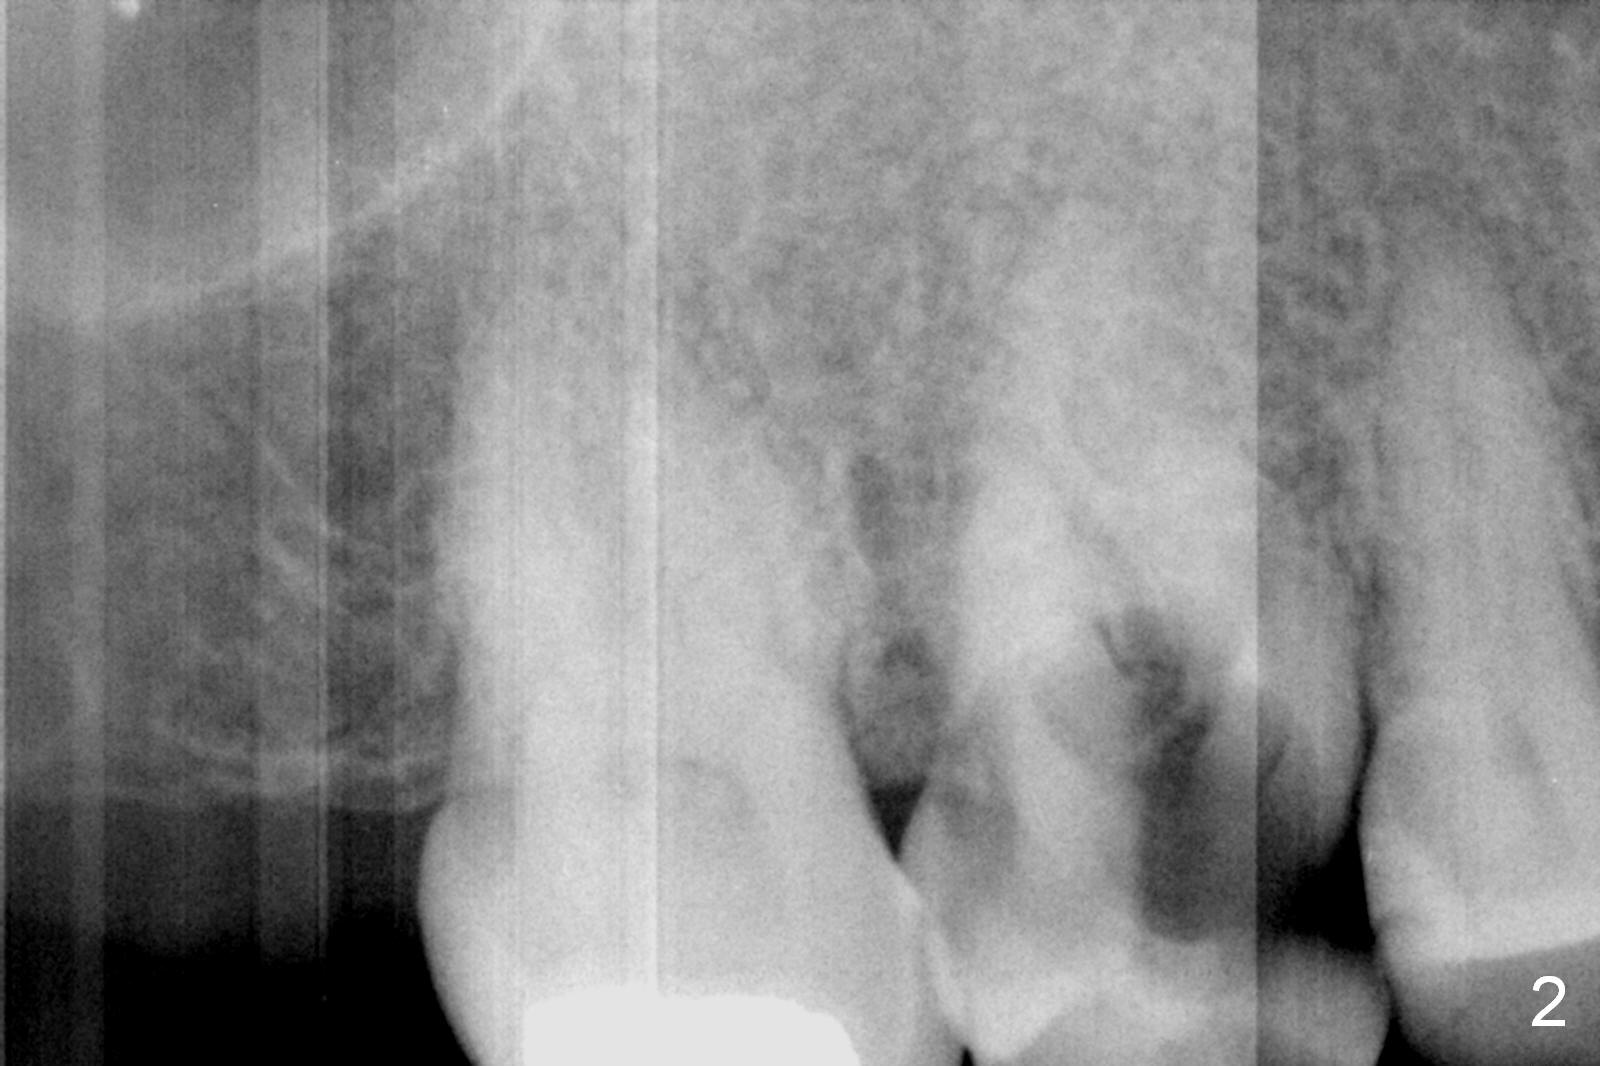

A 52-year-old woman is a dental phobic.  Her main concern is the tooth #3 with caries apparently involving the furca (Fig.1 ^).  Before extraction, take photos to show a polyp in the pulpal chamber, which is most likely periodontal.  After extraction (prepare surgical handpiece, since the tooth most likely fractures at extraction), take photos to show furcal perforation, while the socket is packed with 3 pieces of gauze soaked with Metronidazole.  There is apparently sufficient bone apical to the roots (Fig.2).  To achieve primary stability, use an implant as long as possible (13 mm of IBS, Fig.3 (implant is drawn to be placed too superficial)) with large diameter appropriate to the septum.  The plateau of the implant will be placed apical to the crests and coronal to the septum.